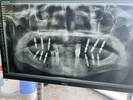

Implant tedavisi